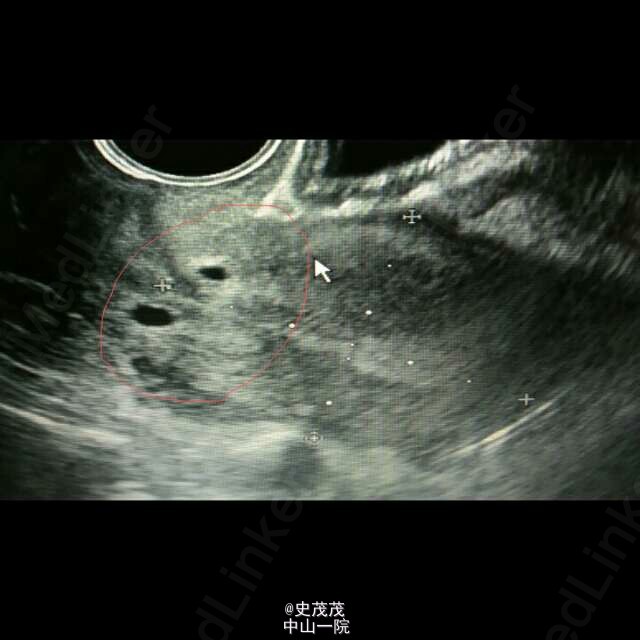

卵巢畸胎瘤蒂扭转

以“下腹痛5天”急诊收入院,外院B超、CT提示卵巢畸胎瘤可能,遂转入我院。已手术,术中见巨大畸胎瘤,内含多量黄色浑浊液,见毛发。快速冰冻,提示含有牙齿。 B超不怎么会看,有个问题:按顺序的发的B超图片,里面有2-3-2个无回声洞,这几个无回声洞可提示蒂扭转吗?(那个洞是输卵管管腔吗?)